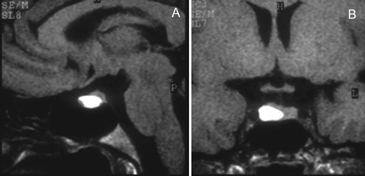

Apoplejía pituitaria

La apoplejía pituitaria (Figuras 21A y 21B) es un síndrome clínico que resulta de una hemorragia aguda o infarto en un tumor pituitario51. En pacientes con macroadenomas no funcionantes la apoplejía es el cuadro de presentación en un 15 a 25% de los casos52. En la minoría de los pacientes con apoplejía se conoce previamente la existencia de un tumor pituitario53. En comparación, la incidencia de apoplejía en pacientes con un tumor pituitario conocido es estimada en menos de 1% por año54. La presencia de sangre en un adenoma pituitario no va siempre acompañada de un cuadro clínico de apoplejía pituitaria y es un hecho frecuente de encontrar (Figuras 22A y 22B); los macroadenomas pueden presentar en el 14% de los casos focos de hiperseñal en TIw en áreas de hemorragia55,56. La evolución temporal de la hemorragia en RM (Figuras 23A, 23B y 23C) es diferente a la hemorragia del cerebro que se reabsorbe en pocas semanas; en la glándula pituitaria la hiperseñal T1w puede mantenerse por largo tiempo57.

Figura 22A y B. Cortes sagital y coronal, secuencia T1w. Se observa un nódulo espontáneamente hiperintenso, resultante de hemorragia subaguda en un adenoma hipofisiario.